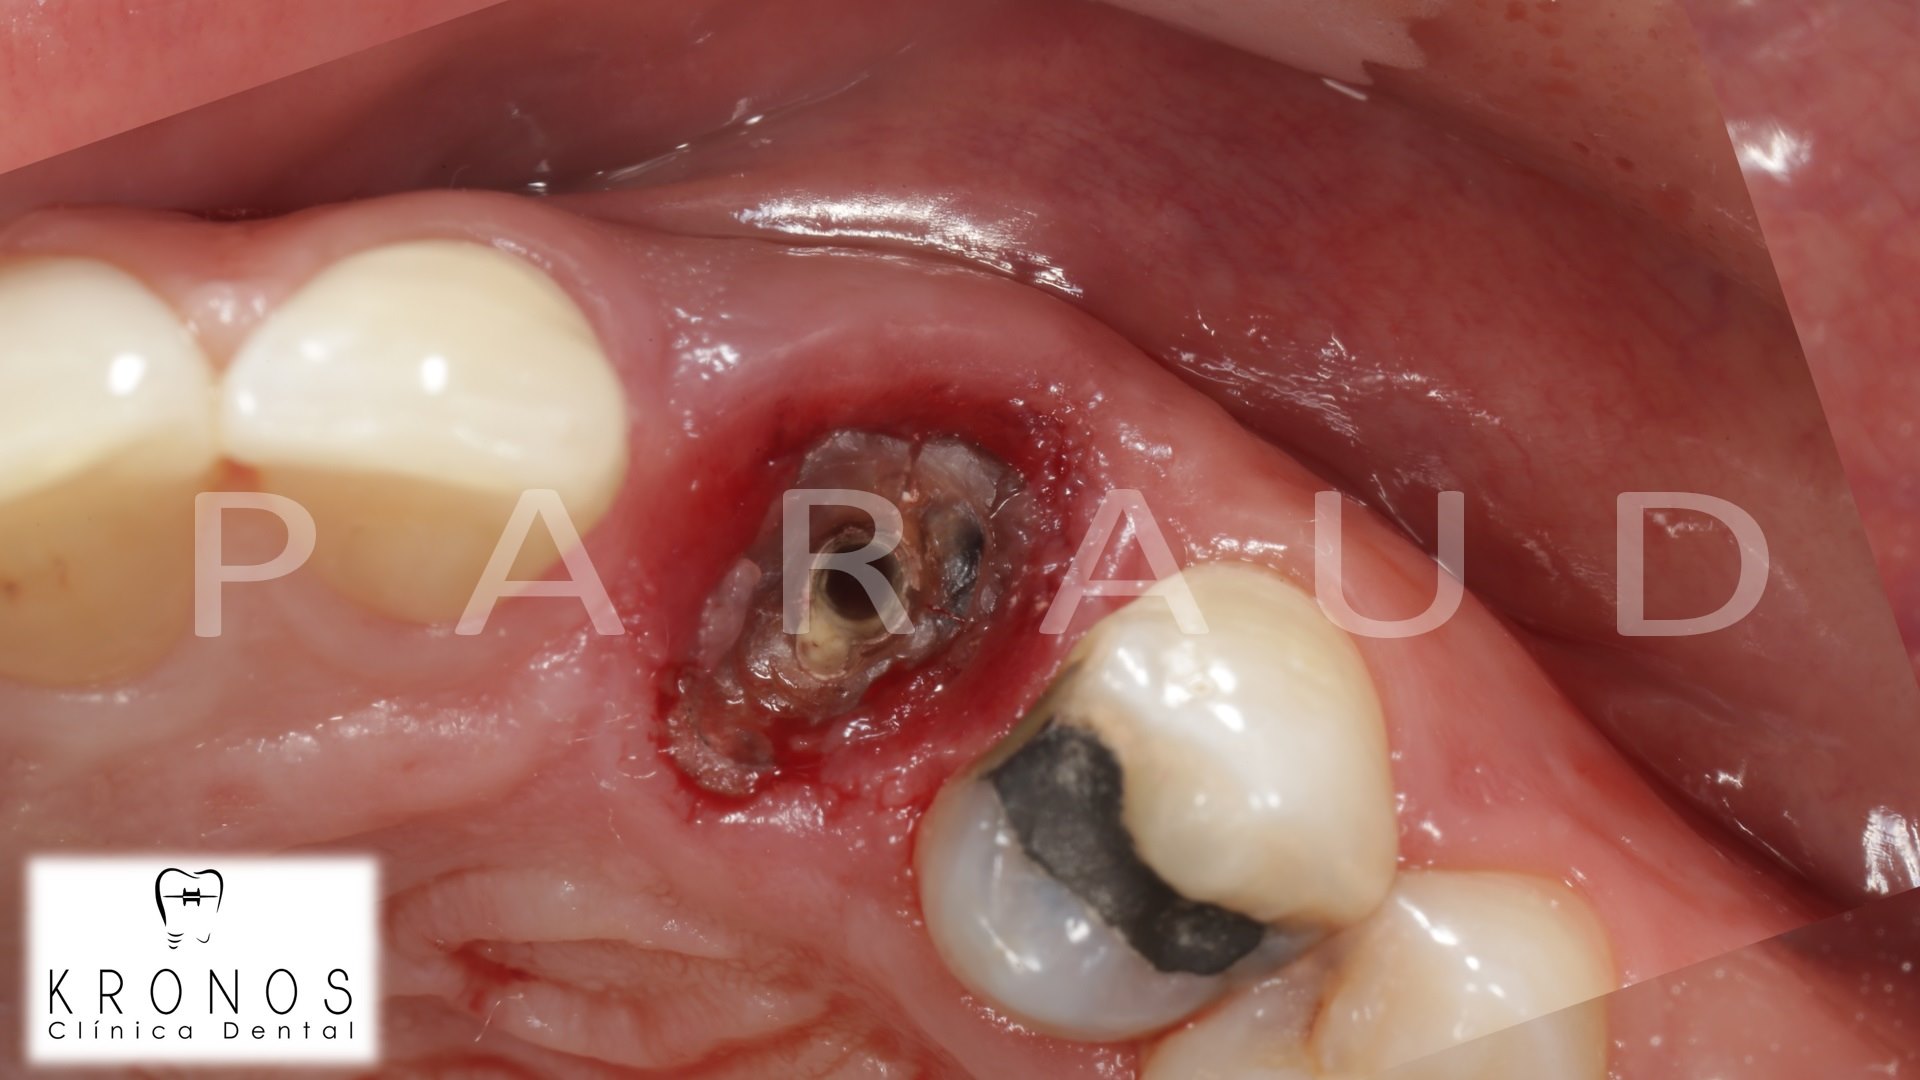

Clinical case: Extraction, immediate implant placement, & provisionalization

- Courtesy of Dr. Iulian Filipov, Romania -

AnyRidge, R2GATE, guided surgery, immediate placement, immediate provisionalization, initial stability, Dr. Iulian Filipov, #25, maxillary posterior, immediate loading, Mega ISQ

AnyRidge implant system, R2GATE, MEGA ISQ, Digital prosthesis